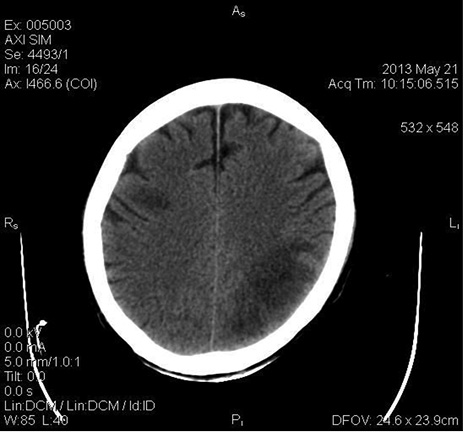

Un mes después del alta hospitalaria, es decir, dos meses luego de la cirugía valvular es valorado por cirugía cardiovascular en consulta externa, observándose en regulares condiciones generales, taquicárdico, polipneico. Se hospitaliza, se inician estudios, documentando nuevamente bacteriemia por P. aeruginosa resistente, razón por la cual se sospecha posibilidad de EI. Se realiza ecocardiograma transesofágico, hallando vegetación adherida a la prótesis biológica de la válvula aórtica, 9 mm (ver Figuras 1-2). Por alteraciones comportamentales concomitantes se ordena una tomografía computarizada (TC) cerebral, observando una zona de hipodensidad que compromete el lóbulo parietal izquierdo y en la topografía de la corteza pre-motora derecha, borramiento de surcos cerebrales, hallazgos compatibles con infartos subagudos probablemente de origen embólico (ver Figura 3) y, por descenso progresivo de hemoglobina sin foco claro, asociado a ascitis, se realiza TC contrastado de abdomen, documentando una zona de infarto segmentario a nivel del polo superior del bazo (ver Figura 4), interpretado como embolismo séptico.

Figura 3: Infartos subagudos probablemente de origen embólico.